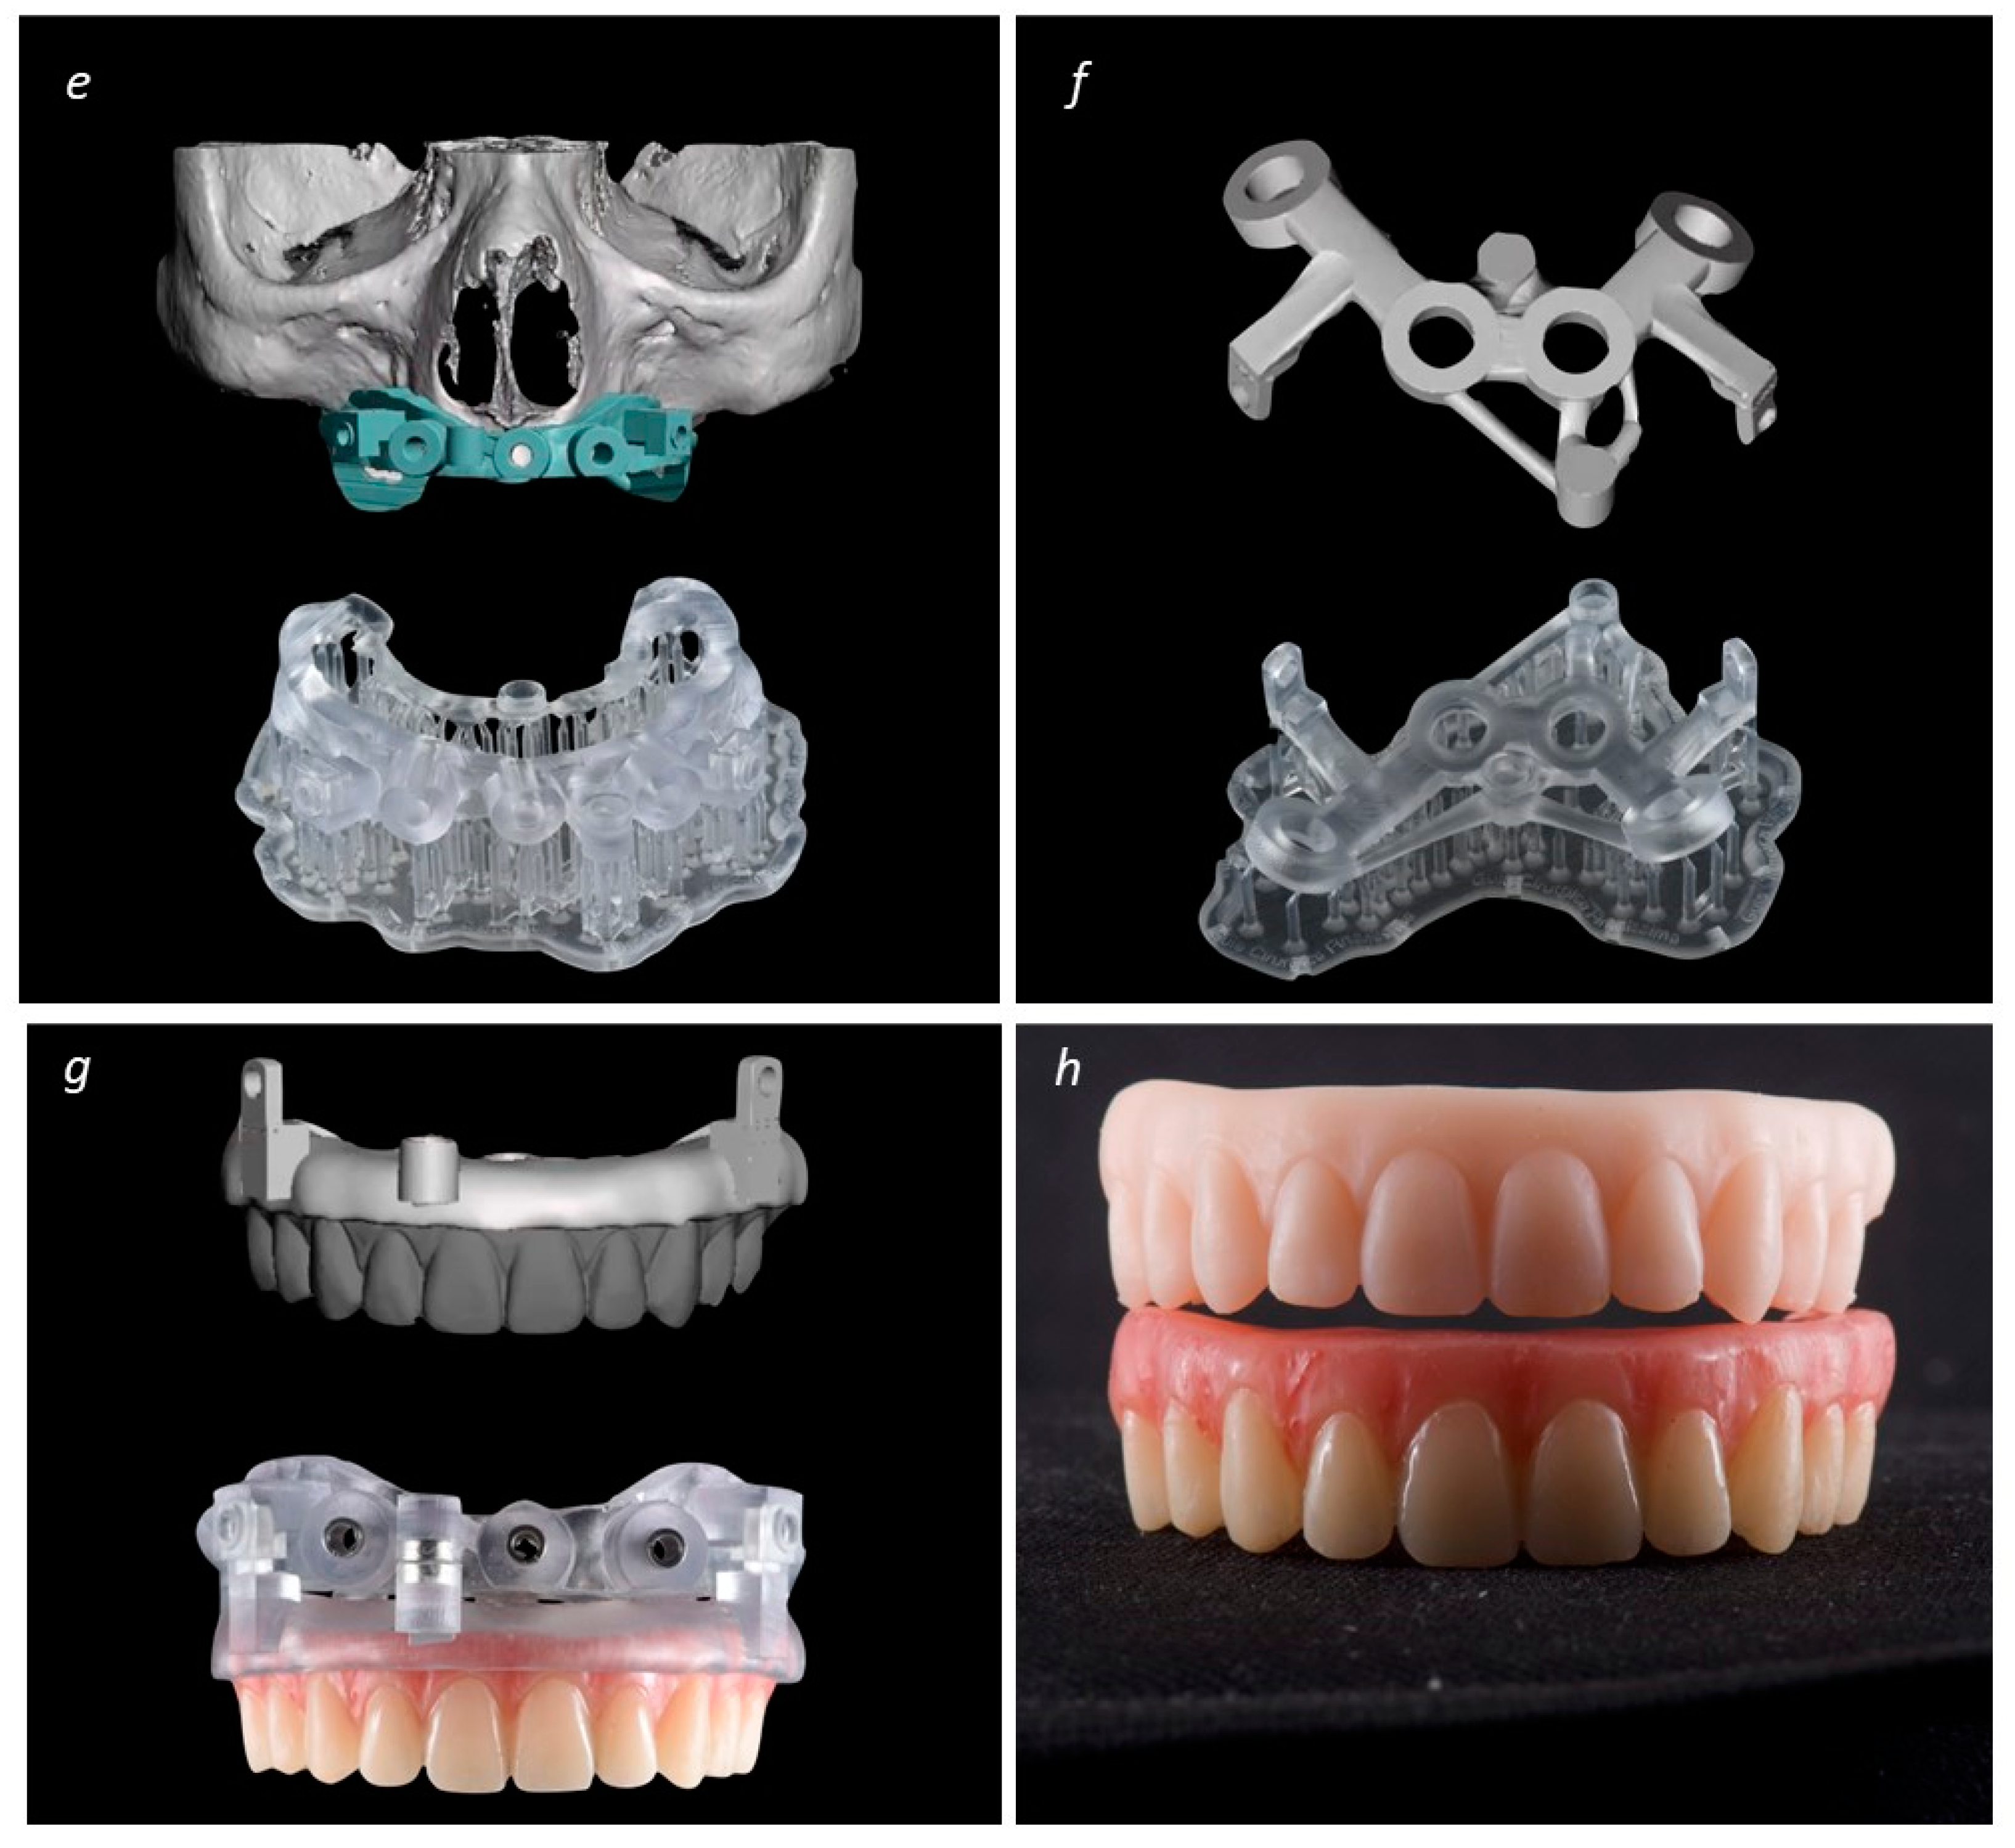

2. Materials and Methods

Description of the Technique

3. Results